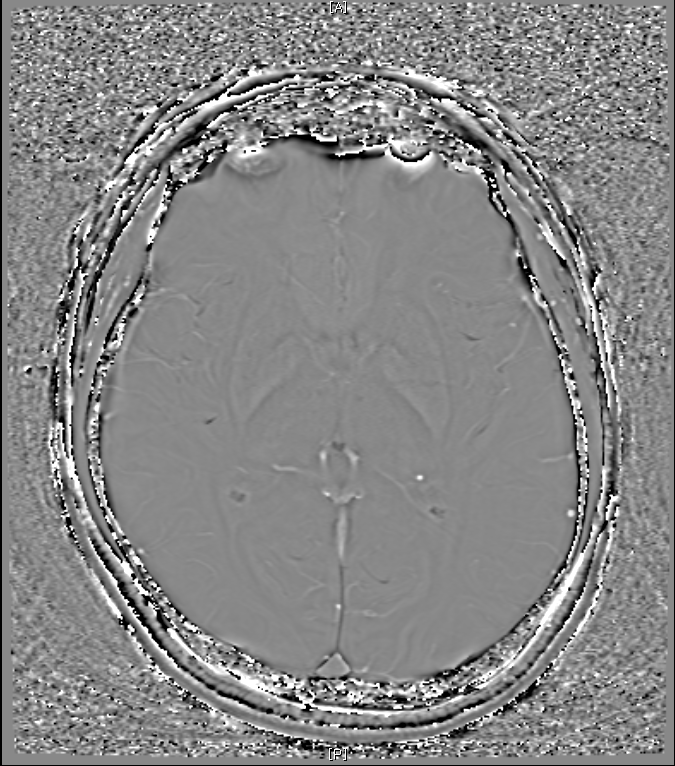

지난 금요일에 MRI를 촬영했는데요

혈관같기도 하고 하얀색 붕붕 뜨는 게 있어보이는데 (혈관같음)

한번 봐주실수 있나요? 그리고 전체적으로 괜찮은지도 봐주시면 감사하겠습니다.

특별하게 눈에 띄는 병변은 있어보이지 않습니다

말씀하신 것은 혈관의 가능성이 높겠습니다